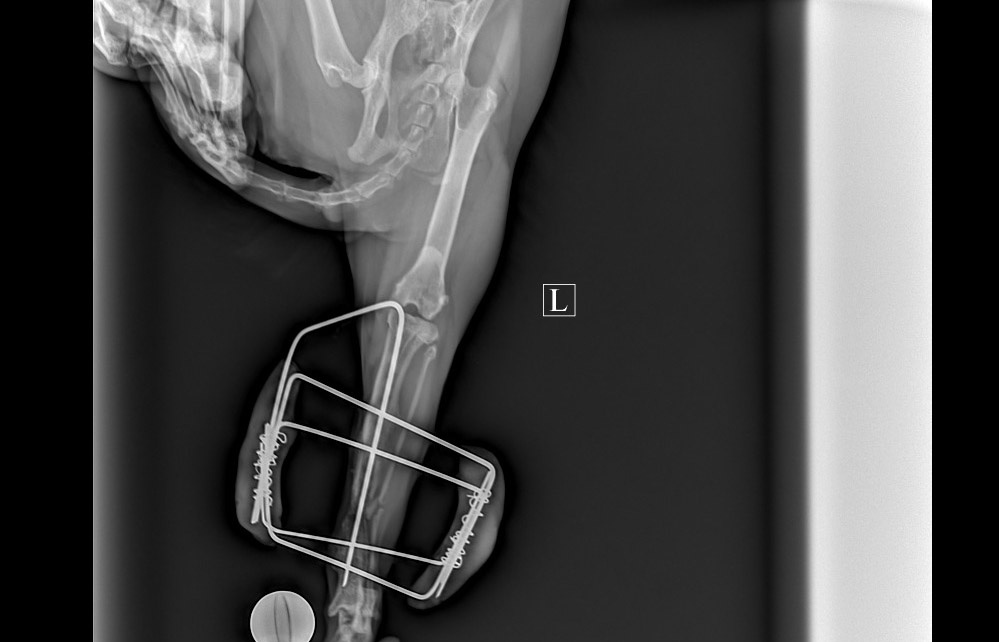

Панкрат из тех, кто спасает себя сам. Ну есть такие хвостики, которые знают, куда идти, если плохо. Вот он и пришёл в конце лета к одной клинике, попросил помощи. Хромал и плакал. Помощь оказали тут же - оказалось, что сломана задняя лапка. На следующий же день ему установили фиксатор на лапку, сказали, перелом "хороший" срастись должно будет отлично. Через месяц - полтора - убираем фиксатор.

Вчера снова снимок и снова картина та же. Врач удивился, как будто вчерашний перелом. Никаких признаков ухудшения, но и заживления нет. Вообще. Ни костных мозолей, ничего, чтобы хоть как-то на положительную динамику указало.

Предложили еще вариант - убрать фиксатор и установить интрамедуллярный штифт. Он как раз для сращивания длинных костей, подходит больше чем фиксатор.